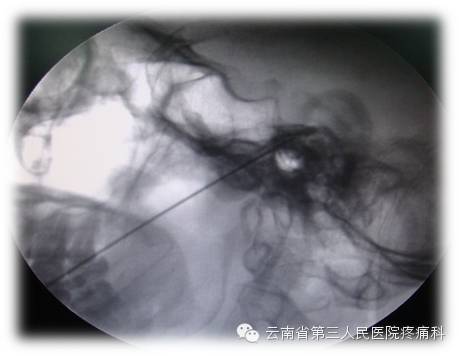

我科熟练开展经卵圆孔半月神经节射频热凝治疗

经皮穿刺半月神经节射频热凝术是治疗三叉神经痛最有效方法之一

治疗原理:三叉神经为感觉神经,其中神经纤维(AA纤维和AB纤维)能耐受较高温度,而痛觉神经纤维不能耐高温,CT引导三叉神经热凝术选择破坏痛觉纤维,使患者疼痛治愈。

治疗优势:安全、疗效好、不易复发、无副作用、费用比手术治疗低、创伤小、痛苦小、治疗时间短。

此项技术的重要环节在于靶点穿刺的准确性,利用CT引导或3维重建技术,可以使穿刺成功率和有效性大大提高。证疗效及安全的另一重要环节为热凝温度选择科学性。